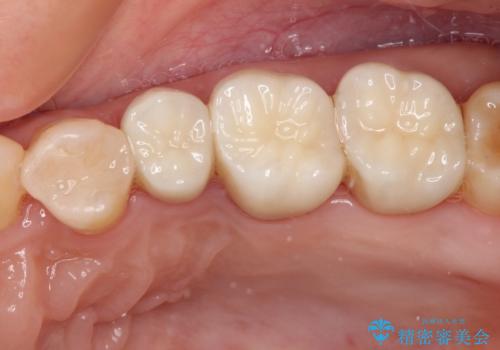

知覚過敏の症状はなくなり、希望通りの白い歯になったと、患者様は大変満足されました。